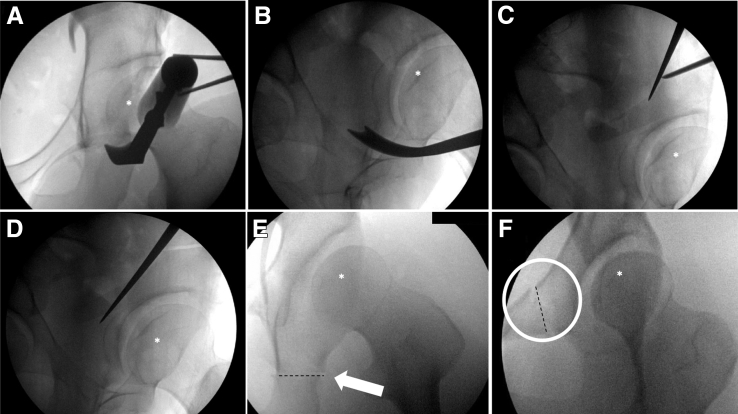

Fig 5.

(A) Anteroposterior and (B) false-profile views used during the ischial cut for left hip periacetabular osteotomy; (C) marking the supra-acetabular and posterior column cuts; and (D) making the posterior column cut., (E) The completed ischial cut marked with an arrow and a dashed line. (F) the completed pubic cut marked with a circle and a dashed line. The femoral head is marked in each of the images (A-F) with an asterisk.